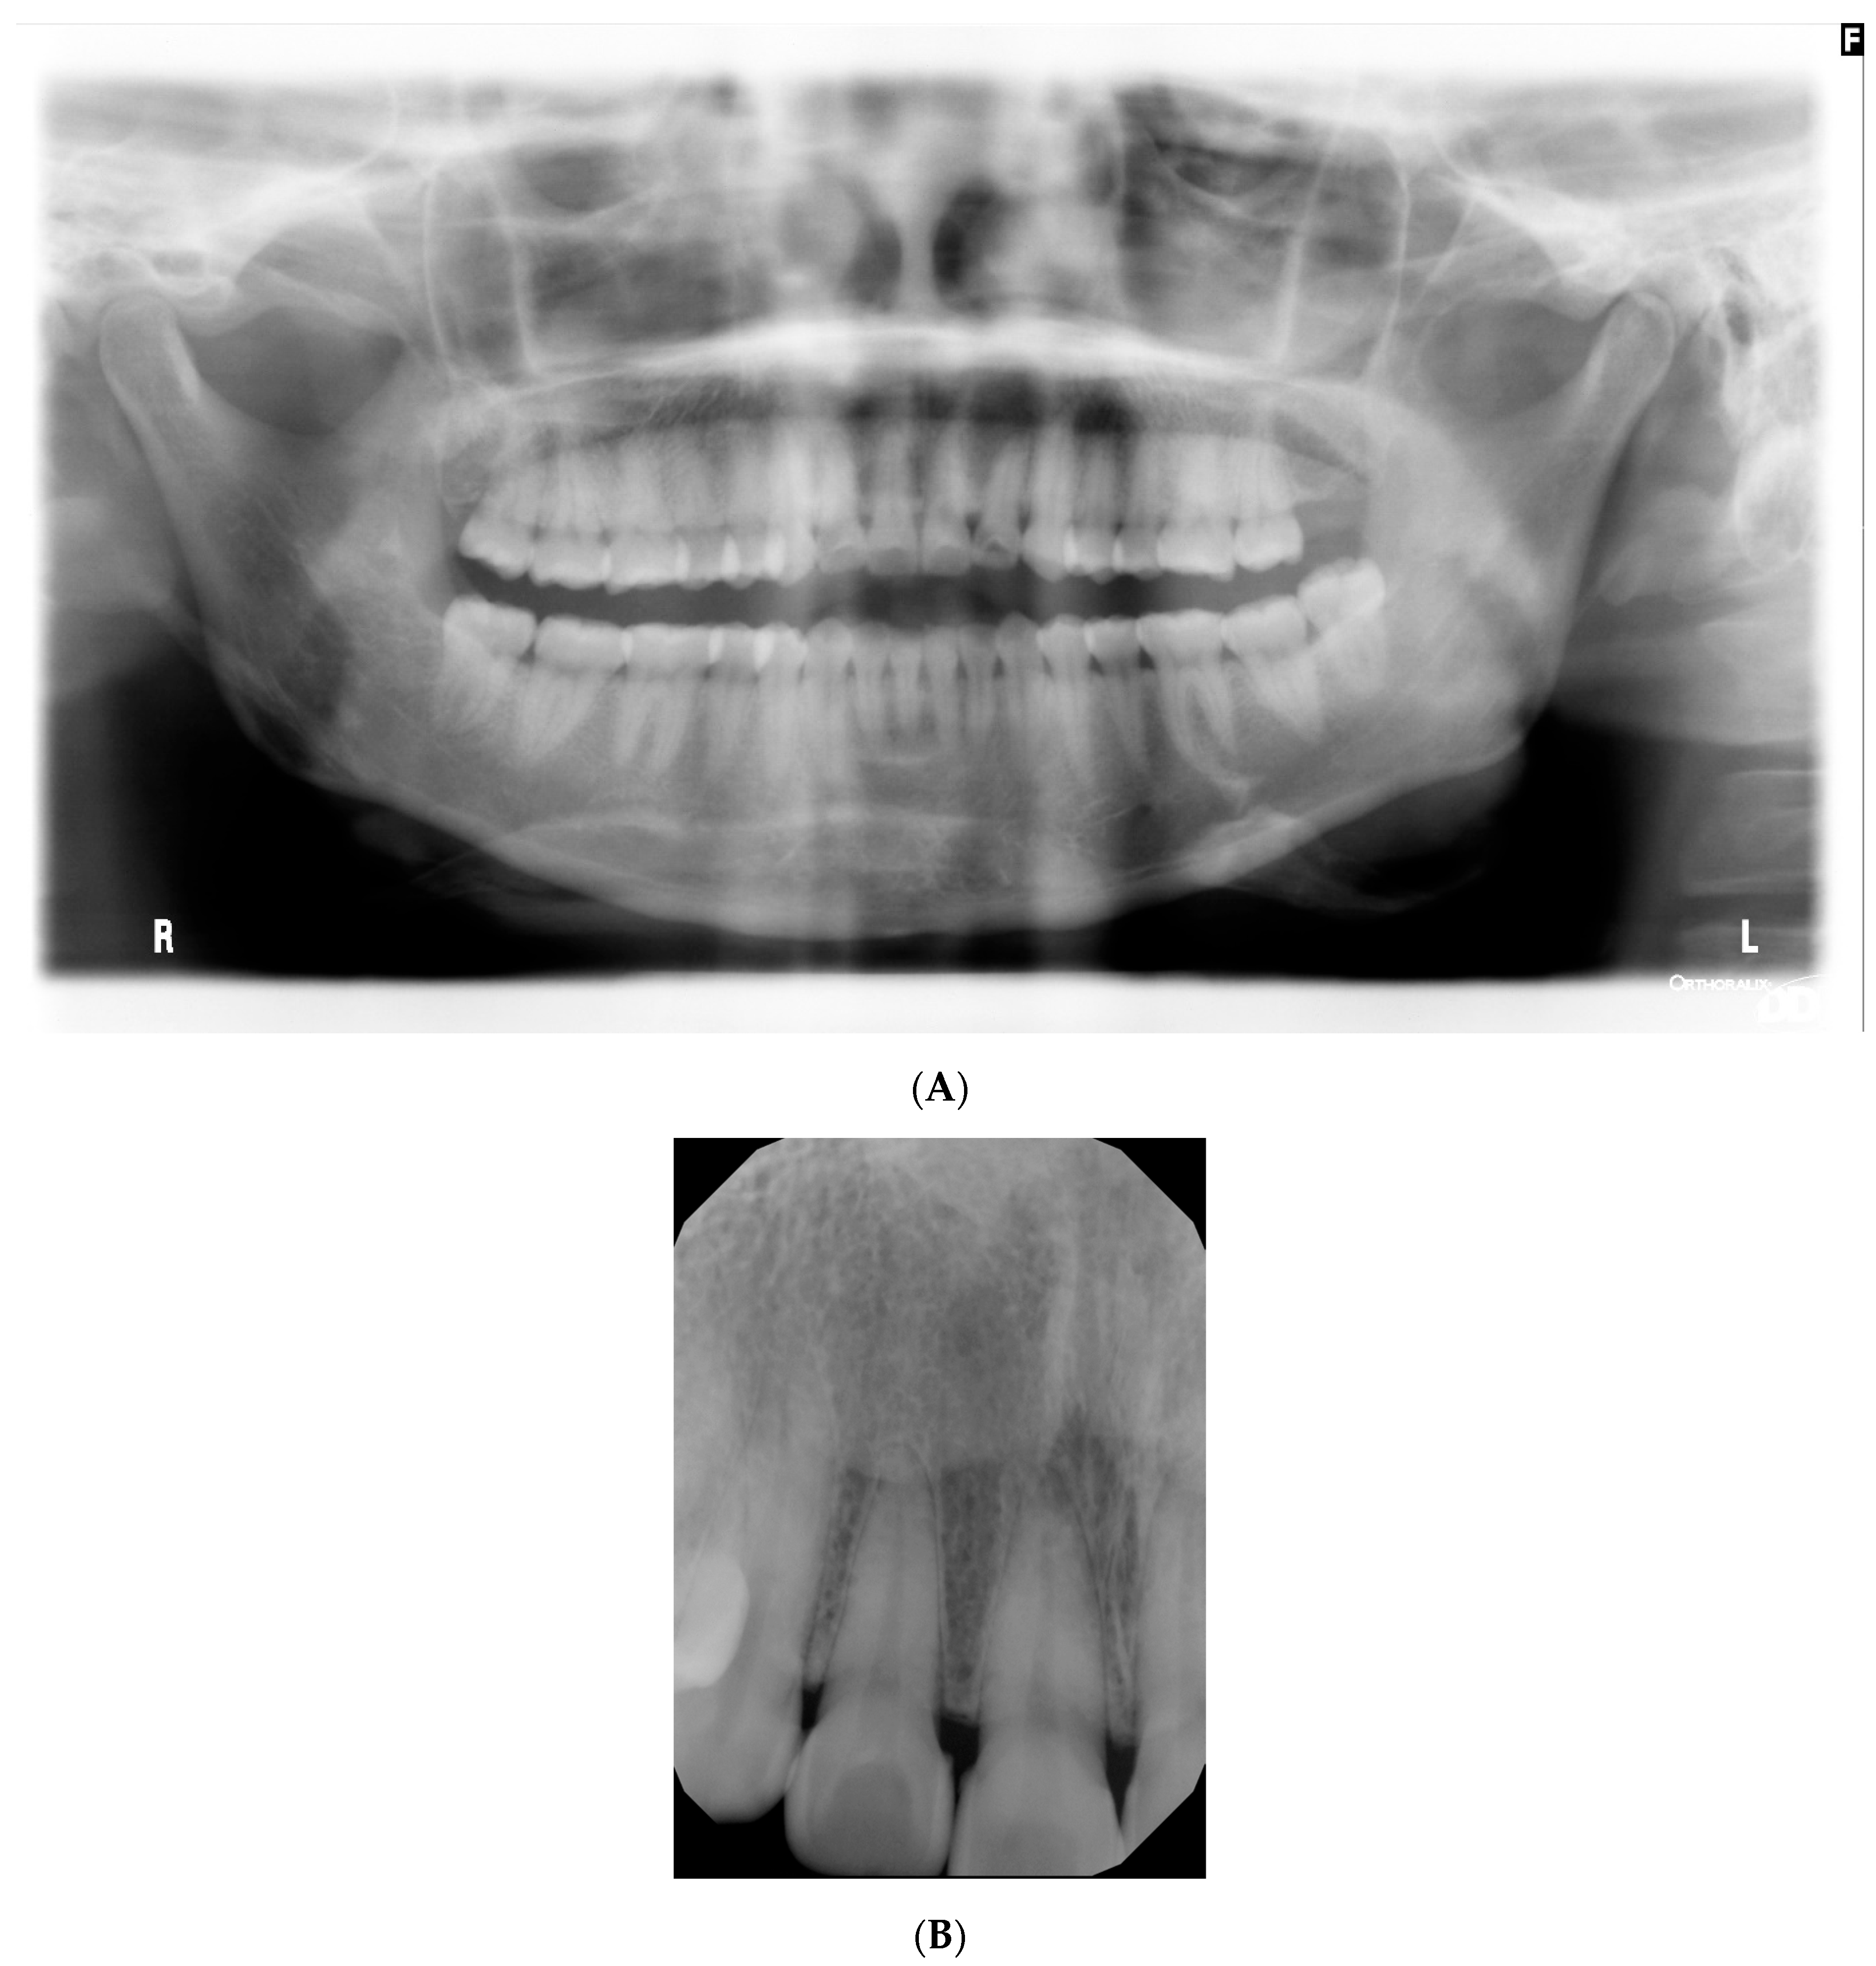

Mixed purple and white necrotic lesions with sloughing were noted around the buccal gingival margins and attached gingiva of all premolars and molars and palatal/lingual gingival margins of all teeth. More photographs are included in the Supplementary Materials (Figure S1). Probing depths were within normal limits, and no mobility or fetid odour was noted. Radiographic examination revealed normal bone levels and no obvious pathology (Figure 2).

Figure 2.

(A) Dental pantomogram taken at initial presentation. (B) Periapical radiograph taken at tooth #11, #12 mild calculus deposits but no radiographic bone loss.